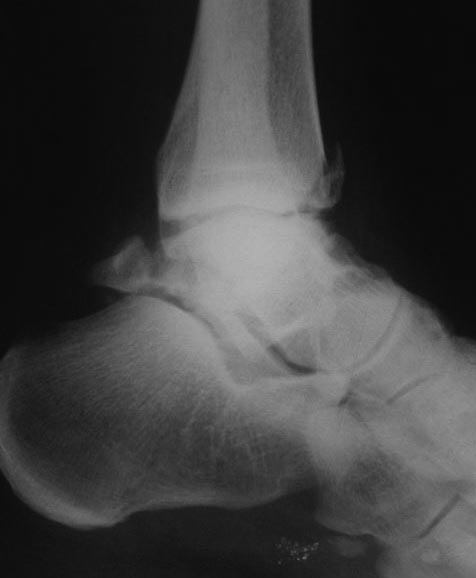

Рентгенограммы после операции

После операции месяц находился в гипсе, ниже рентгенограммы через месяц

Имеются явные признаки консолидации, гипс снят. По-моему прикольно, вместо такой большой операции все делать артроскопически. При этом кровоснабжение таранной кости не нарушается, риск асептического некроза минимизируется.